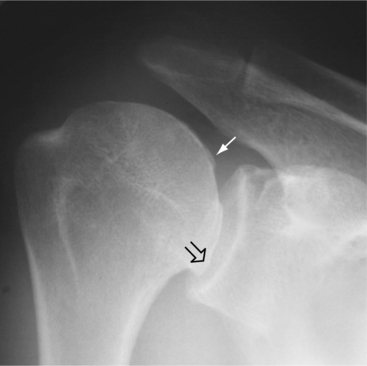

The joint space narrows as the cartilage thins, and sclerosis of the subchondral bone occurs as new bone is formed in response to the now excessive mechanical load. New bone also forms at the joint margins (osteophytes) (Fig. 27-1) with the end result being mechanical joint failure and varying degrees of loss of joint function.

Figure 27-1 A, Early degenerative changes associated with osteoarthritis include joint space narrowing and articular cartilage erosion. B, Late degenerative changes associated with osteoarthritis include osteophyte formation and articular cartilage fissuring and eburnation.

OA is diagnosed by correlation of history, physical examination, radiologic findings (Figs. 27-3 and 27-4), and laboratory tests, which rule out rheumatic disease. Box 27-6 lists radiographic changes associated with OA. The history of location of symptoms, symptom duration, functional limitations, trauma, medical comorbidities, and family history helps guide the physician in making the diagnosis.

Figure 27-3 Osteoarthritis of the shoulder. There is osteophytic lipping (open arrow) from the humeral head, including new bone formation deep to the cartilage (closed arrow). (From Harris ED: Kelley’s textbook of rheumatology, ed 7, Philadelphia, 2005, Saunders.)